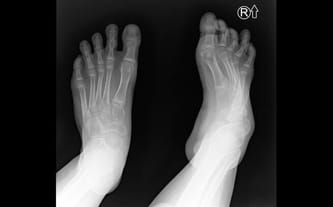

Cel zbiórki: Operacja ortopedyczna w Paley European Institute

Mózgowe porażenie dziecięce, stan po selektywnej rizotomii grzbietowej, niedowład spastyczny kończyn dolnych, mukowiscydoza